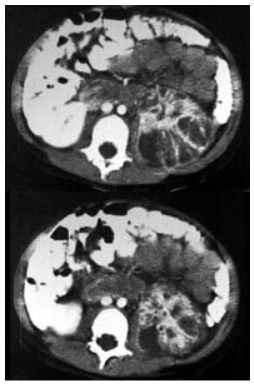

男,5岁,有尿路感染伴急性发热,CT增强扫描如图所示,最可能诊断为 ( )

• A、左侧肾炎

• B、左侧肾脓肿

• C、左侧急性肾盂肾炎

• D、左侧黄色肉芽肿性肾盂肾炎

• E、左侧慢性肾盂肾炎